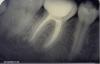

Kivilgar Опубликовано 23 октября, 2009 Поделиться Опубликовано 23 октября, 2009 Господа стоматологи!Такая ситуация-пациенту 43 года,18 августа 27з периодонтит, http://i050.radikal.ru/0910/e2/cbc56963e190.jpg ,без симптомов,4 канала,закрыл под Кемфил с Каласептом изза нехватки времени.Обработка-гейтсы,руки,долго ультразвук,гипохлорит,рс-преп.За апексом был 10 файлом при определении длины.Пациент пропал на 2 месяца,объявился 21 октября-зуб не болел,я запломбировал и увидел,что периапикальные изменения как бы уменьшились. http://s09.radikal.ru/i182/0910/0c/104458fb287b.jpg Но че-то мне в это не верится http://s54.radikal.ru/i143/0910/96/032f4a160deb.jpg .Скорее такой вид изза другой проекции,или 2 месяцев всетаки хватит для положительной динамики? http://s09.radikal.ru/i182/0910/13/561a64077c6c.jpg И самое главное подскажите-как эпителизация кист влияет на восстановление периапикальных структур,как определить выстлана резорбция эпителием или нет и в каких случаях это бывает?Каков прогноз лучше-гранулирующий или гранулематозный?Особенно хотелось бы услышать Inspiration и Fred.Если кто знает где почитать дайте ссылку.Модераторы-если этот вопрос разбирался,удалите и ссылку. Ссылка на комментарий

nigoda Опубликовано 23 октября, 2009 Поделиться Опубликовано 23 октября, 2009 Здраствуйте , Извините меня для мой руский язык , но я очень давно в школе учил ... Не хотел новую тему открывать , поетому здесь пишу . Какая прогноза етот зуб - я его пролечил , нет боль , но я такой апикалной патологии не увидел до тех пора . Спасибо !!! Ссылка на комментарий

nigoda Опубликовано 24 октября, 2009 Поделиться Опубликовано 24 октября, 2009 Как можно дават прогноз, не зная протокола лечения? Я сделал релечение - МХО - гипохлорид , EDTA , ручные к-файлов с наконечник W&H ,ручные GT 6'и 8' , латерална конденсация с ADseal . У пациента нет боль впереди и потом релечения . Ссылка на комментарий